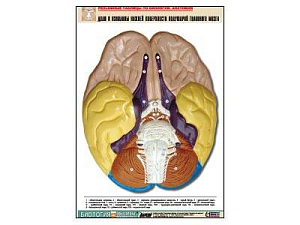

Объёмные модели и муляжи. Модель клетки, скелеты позвоночных, муляжи внутренних органов человека, барельефные таблицы по разделам зоологии и ботаники. На ЕГЭ и ОГЭ задания по анатомии и систематике — одни из самых частых. Объёмная модель отрабатывает пространственное представление так, как плоская картинка не может.